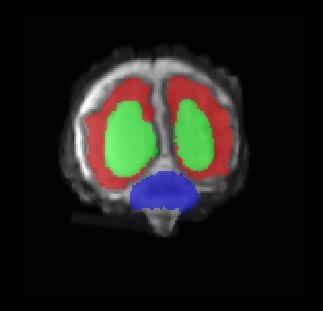

Limiting failures of machine learning systems is of paramount importance for safety-critical applications. In order to improve the robustness of machine learning systems, Distributionally Robust Optimization (DRO) has been proposed as a generalization of Empirical Risk Minimization (ERM). However, its use in deep learning has been severely restricted due to the relative inefficiency of the optimizers available for DRO in comparison to the wide-spread variants of Stochastic Gradient Descent (SGD) optimizers for ERM. We propose SGD with hardness weighted sampling, a principled and efficient optimization method for DRO in machine learning that is particularly suited in the context of deep learning. Similar to a hard example mining strategy in practice, the proposed algorithm is straightforward to implement and computationally as efficient as SGD-based optimizers used for deep learning, requiring minimal overhead computation. In contrast to typical ad hoc hard mining approaches, we prove the convergence of our DRO algorithm for over-parameterized deep learning networks with ReLU activation and a finite number of layers and parameters. Our experiments on fetal brain 3D MRI segmentation and brain tumor segmentation in MRI demonstrate the feasibility and the usefulness of our approach. Using our hardness weighted sampling for training a state-of-the-art deep learning pipeline leads to improved robustness to anatomical variabilities in automatic fetal brain 3D MRI segmentation using deep learning and to improved robustness to the image protocol variations in brain tumor segmentation. Our code is available at https://github.com/LucasFidon/HardnessWeightedSampler.